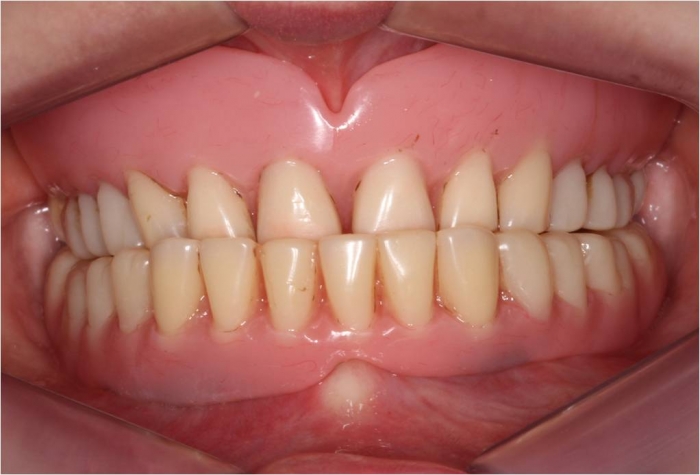

Imagem após prótese imediata inferior e nova prótese superior, provisórias instaladas - Clínica Cliniface

Imagem após prótese imediata inferior e nova prótese superior, provisórias instaladas

Imagem após prótese imediata fixa inferior e nova prótese superior, provisórias instaladas - Clínica Cliniface

Imagem após prótese imediata fixa inferior e nova prótese superior, provisórias instaladas